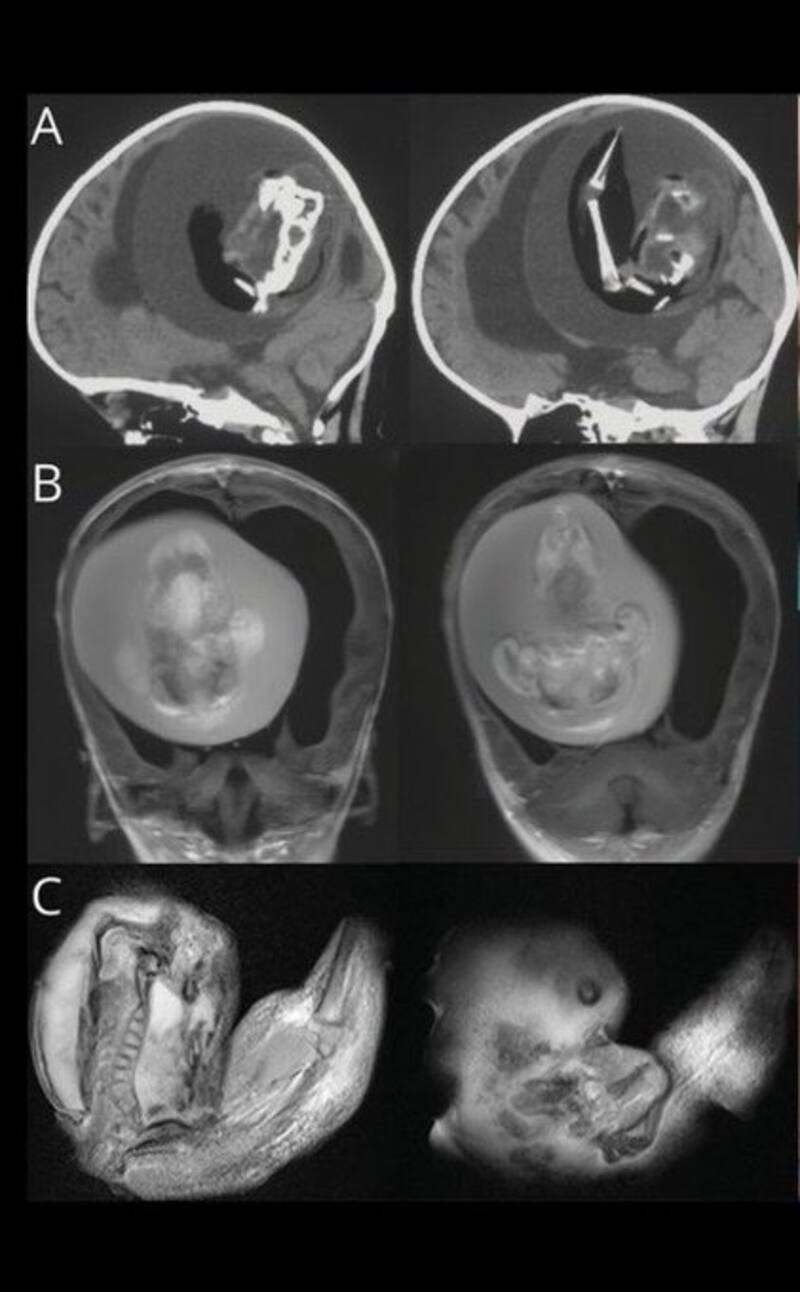

La pequeña mostraba un retraso en el desarrollo de las habilidades motoras y la circunferencia craneal un poco más grande de lo normal. Cuando le retiraron el feto, este tenía sus brazos e incluso algunos dedos.

“Los estudios revelaron que el feto contenía una columna vertebral y dos huesos de la pierna, concretamente el fémur y la tibia, junto a “brotes” en forma de extremidades superiores y dedos”, declaró.